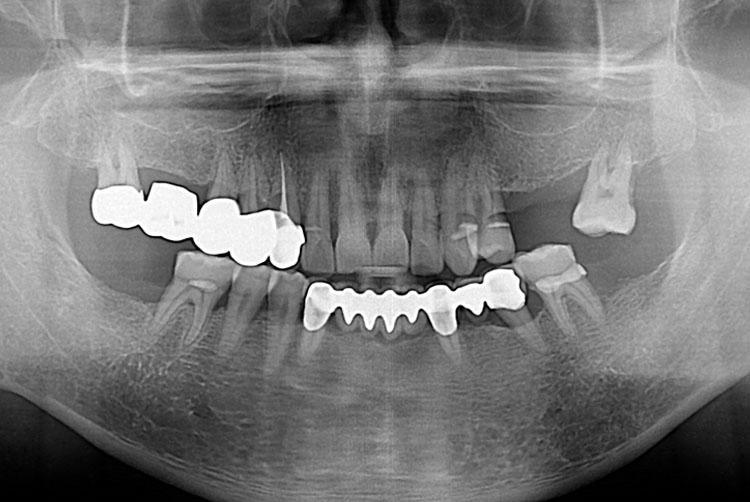

[임플란트] 임플란트

치료후 : 2018-09-27

세종치과는 많은 환자와 다양한 케이스를 바탕으로 항상 편안한 임플란트 수술을 제공하고자 노력하고,

오래동안 튼튼히 쓸 수 있는 임플란트 수술을 가장 큰 목표로 삼고 있습니다.